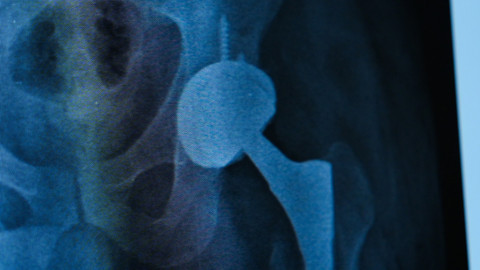

Tedavi süreci hakkında detaylı bilgi veren Prof. Dr. İbrahim Azboy, “Hastamız daha önce protez ameliyatı olmuş ama protezin yerinden çıkması, ardından gevşeme ve çökme sorunları yaşamış. Bu komplikasyonlar üzerine ağrıları devam edince bize başvurdu. Enfeksiyon şüphesiyle yapılan ileri testlerde kalçada ayrıca enfeksiyon tespit ettik. Genelde bu tip durumlarda iki aşamalı cerrahi uygulanır. Bu yöntemde iki ameliyat yapılır. Protez çıkarıldıktan geçici olarak kalçaya çimento konur. İki ay sonra çimento çıkarılıp yeniden protez yerleştirilir. Ancak biz, Zafer beyin protez enfeksiyonunu ‘’Almanya’da geliştirilen tek aşamalı yöntemle tedavi ettik” dedi.

Prof Dr. Azboy sözlerine şöyle devam etti: “Önce enfekte protez çıkarıyor. Daha sonra mekanik debridman denilen yöntemle enfekte dokular etkili bir şekilde temizleniyor. Ardından kimyasal ajanlar kullanılarak iltihaplı bölge dezenfekte ediliyor. Yara geçici olarak kapatılıyor. Tüm setler ve malzemeler dışarı çıkarılıyor. Yeni setler açılıyor. Yeni protez aynı seansta hastaya yerleştiriliyor. Böylece tek ameliyatla hastanın enfeksiyonu tedavi edilmiş oluyor. Böylece hasta kısa sürede ayağa kalkabiliyor, hastanede yatış süresi kısalmış oluyor ve kalça fonksiyonlarını kısa sürede geri kazanıyor. Nitekim, Zafer Bey de ameliyat sonrası hızla yürümeye başladı ve hastaneden kendi aracına kullanarak taburcu oldu.”